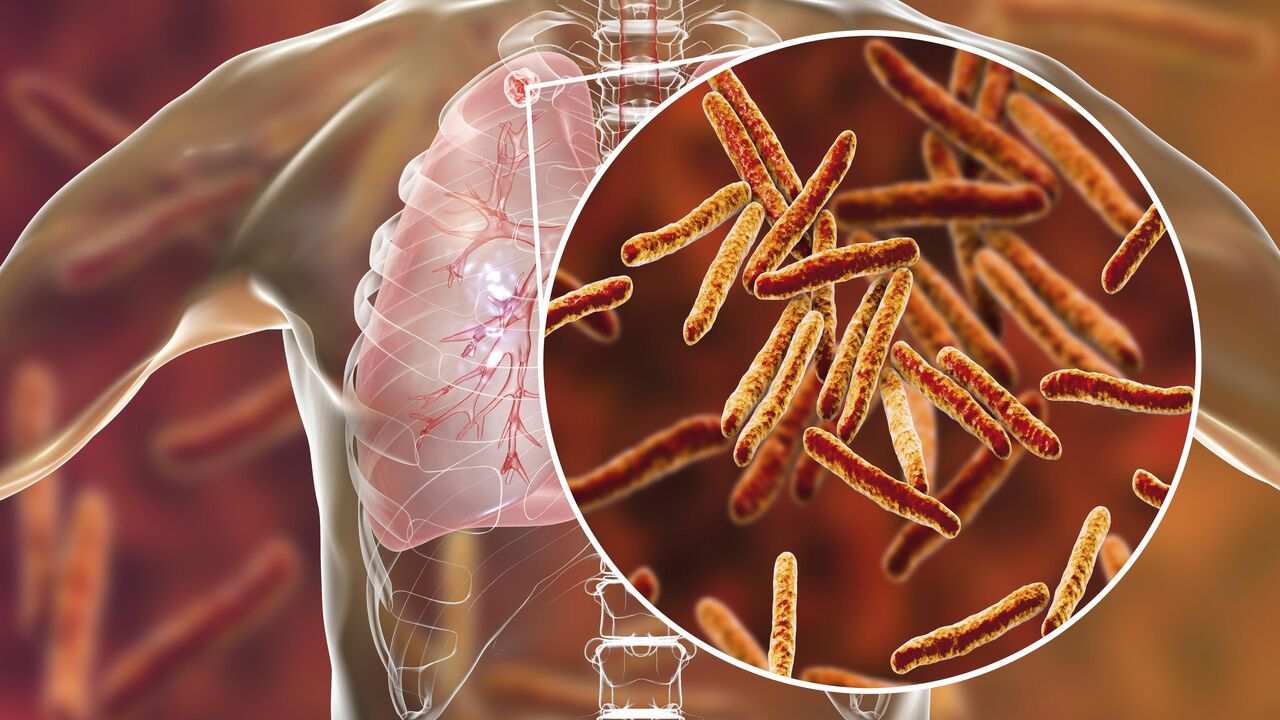

Симптомы и признаки туберкулеза: как распознать заболевание

Раздел: Визуальные уроки